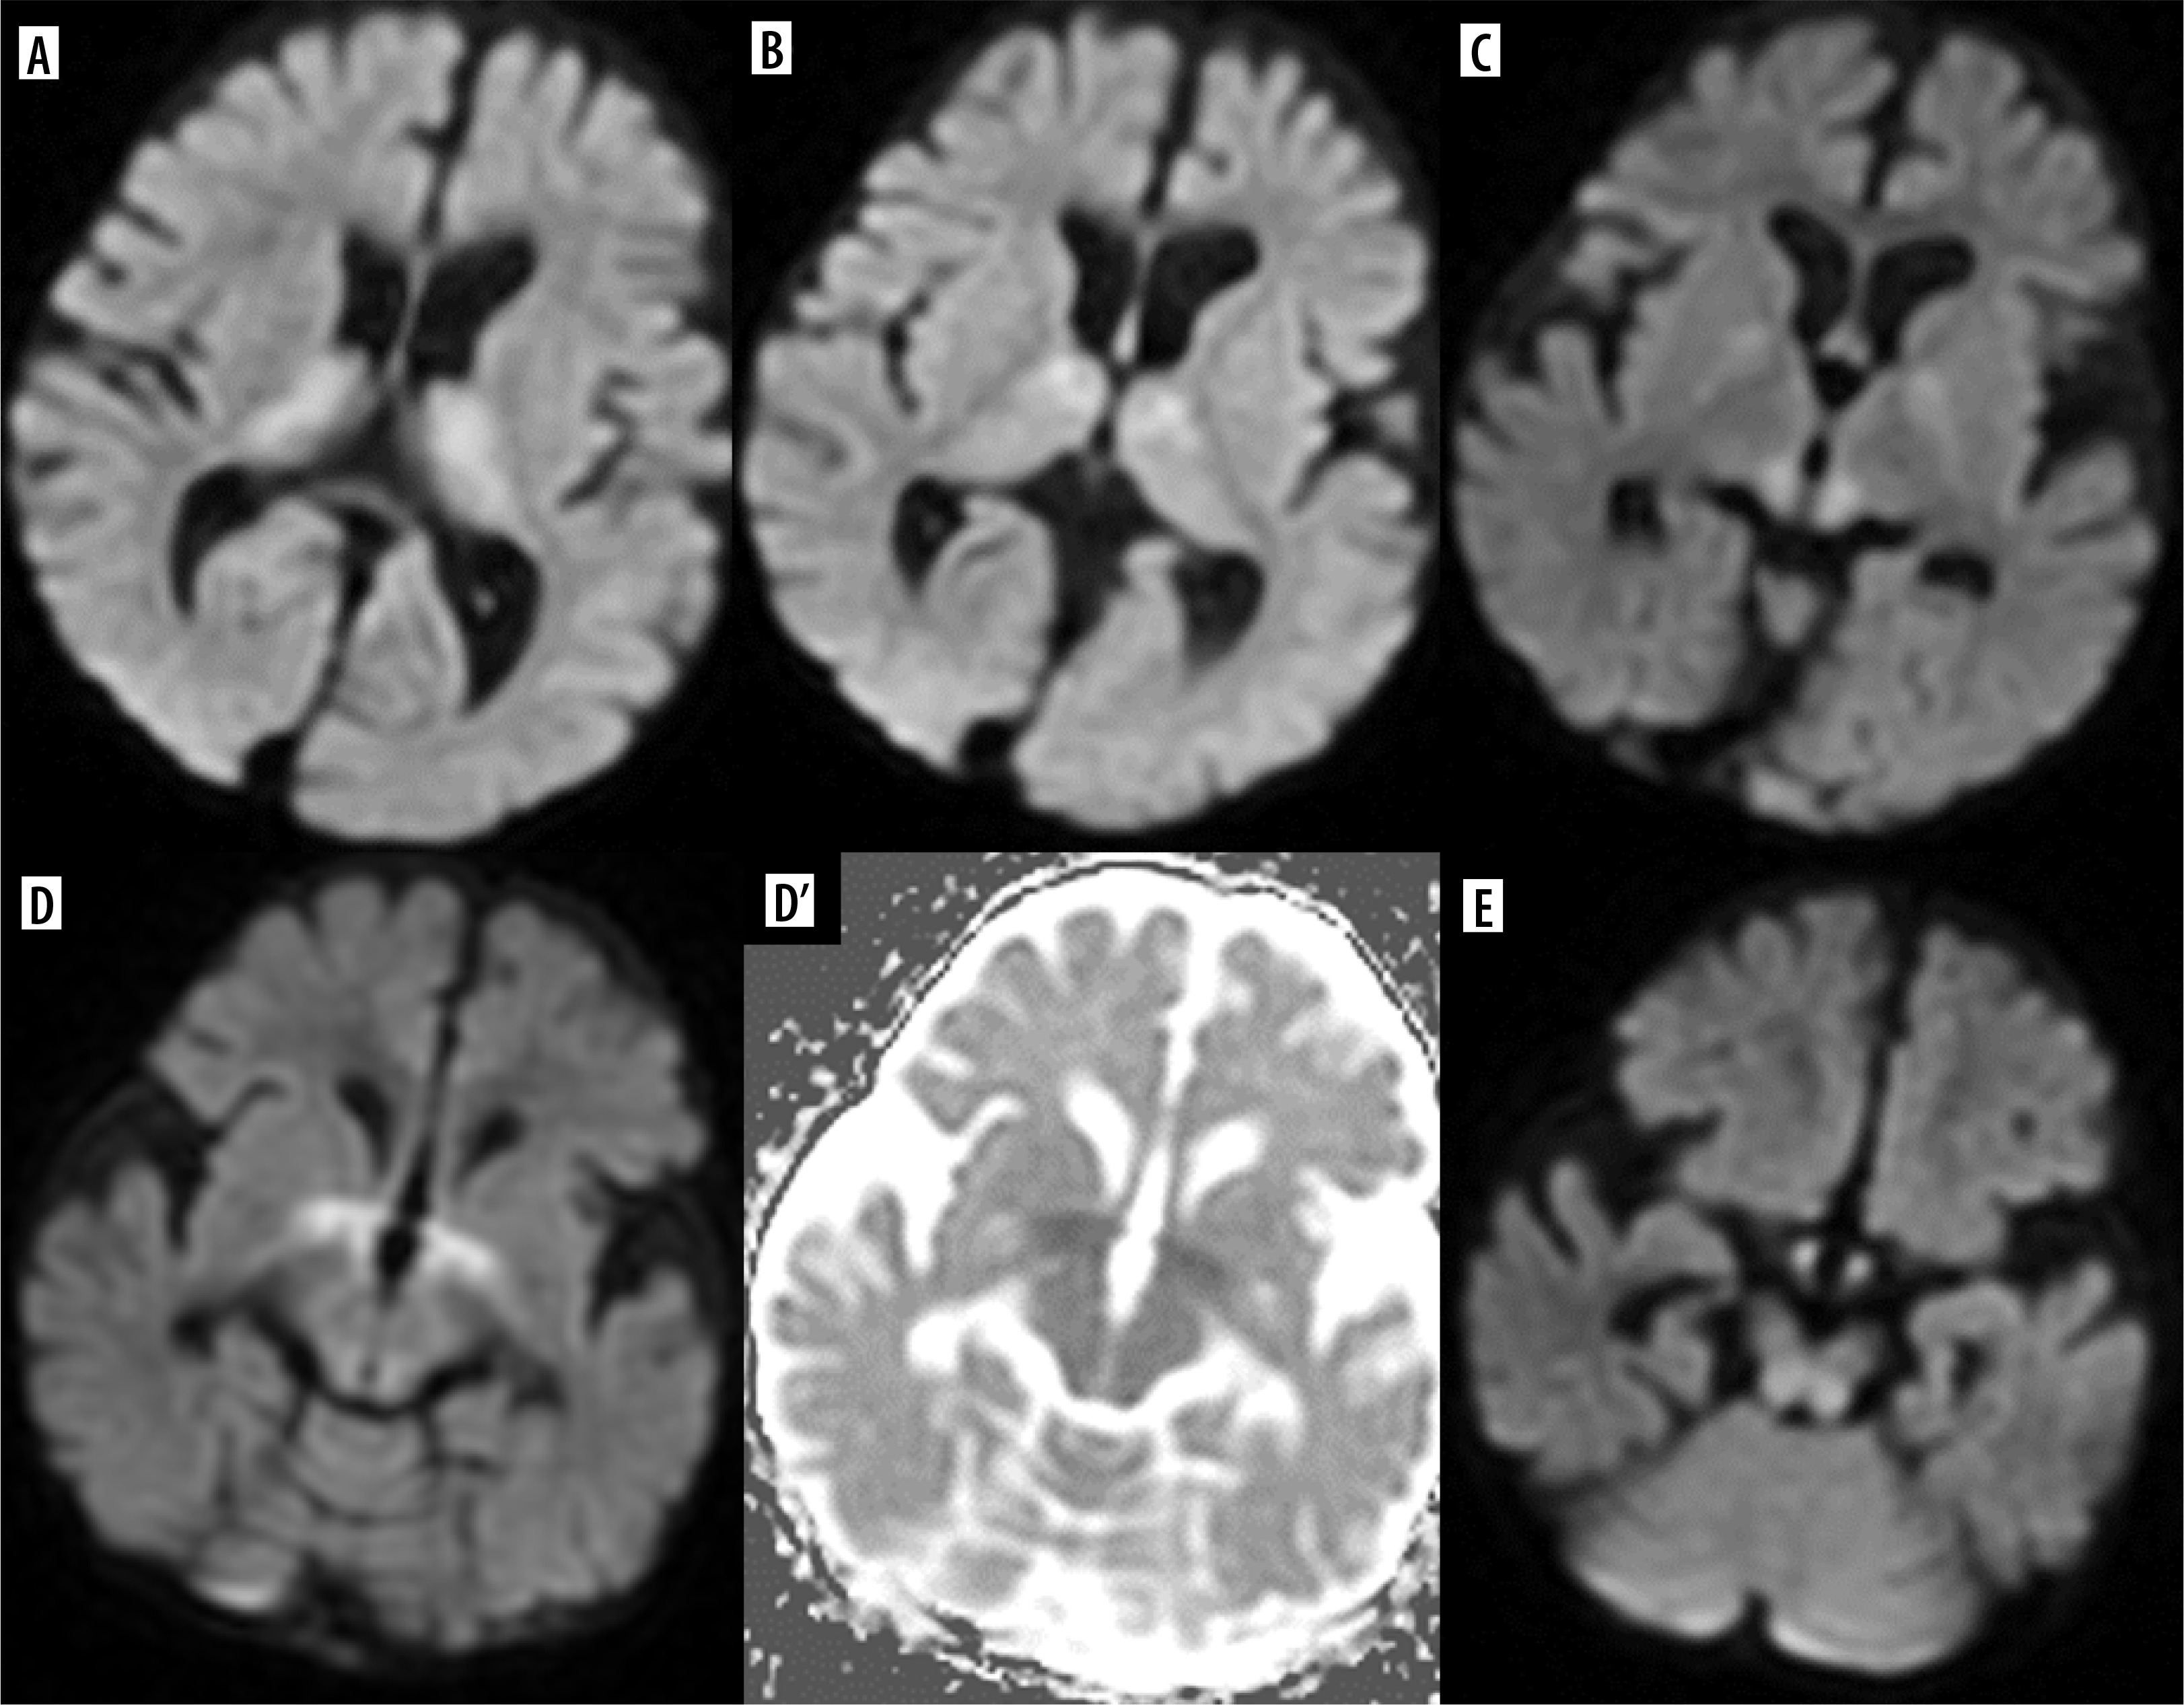

Insulin overdose may lead to cerebral injury due to hypoglycemia with rapid clinical deterioration from dizziness and palpitations to coma. The pattern of brain injury on MRI is bilateral symmetrical in most cases, similar to that seen in hypoxia, but with sparing of the thalamus, cerebellum, and brainstem. Diffusion restriction is found in the cortex of temporal and occipital lobes, of the insulae and hippocampi. The basal ganglia may be involved, and this is associated with a worse prognosis. Less commonly, T2 hyperintensity of the internal capsule, corona radiata, and splenium may also be seen, as well as isolated involvement of the white matter [29] (Figure 11).

Figure 11

Consecutive FLAIR images (A-H) of the brain of a 63-year-old hypoglycemic coma survivor. Symmetrical involvement of the white matter, including the corpus callosum (D, E)